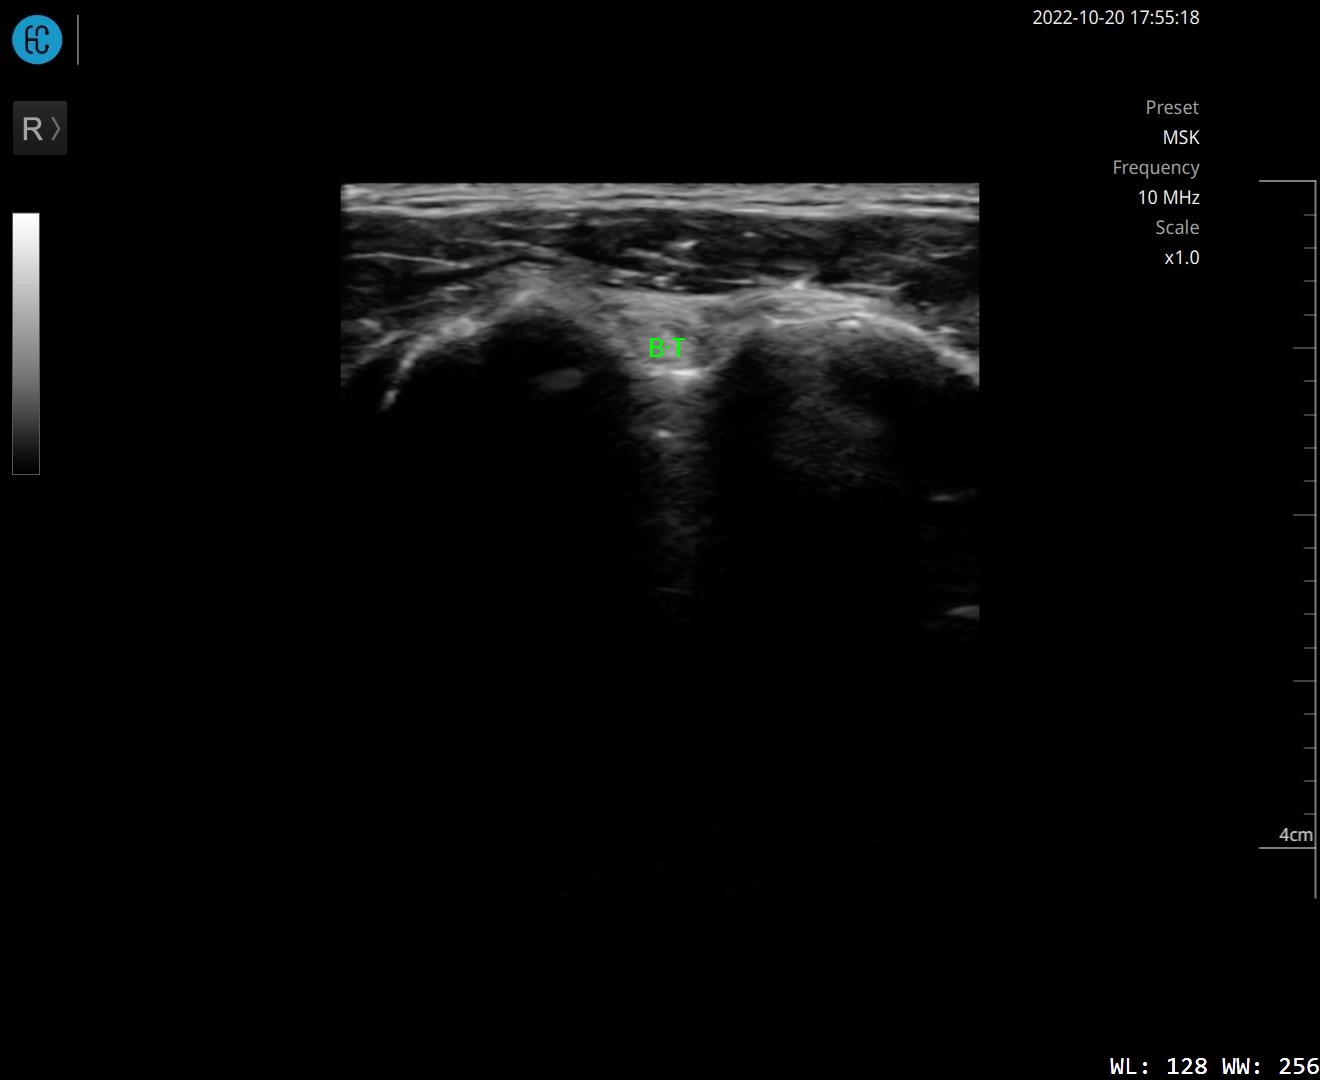

SONON 500L ecografía 1 SONON 500L ecografía 2 SONON 500L ecografía 3